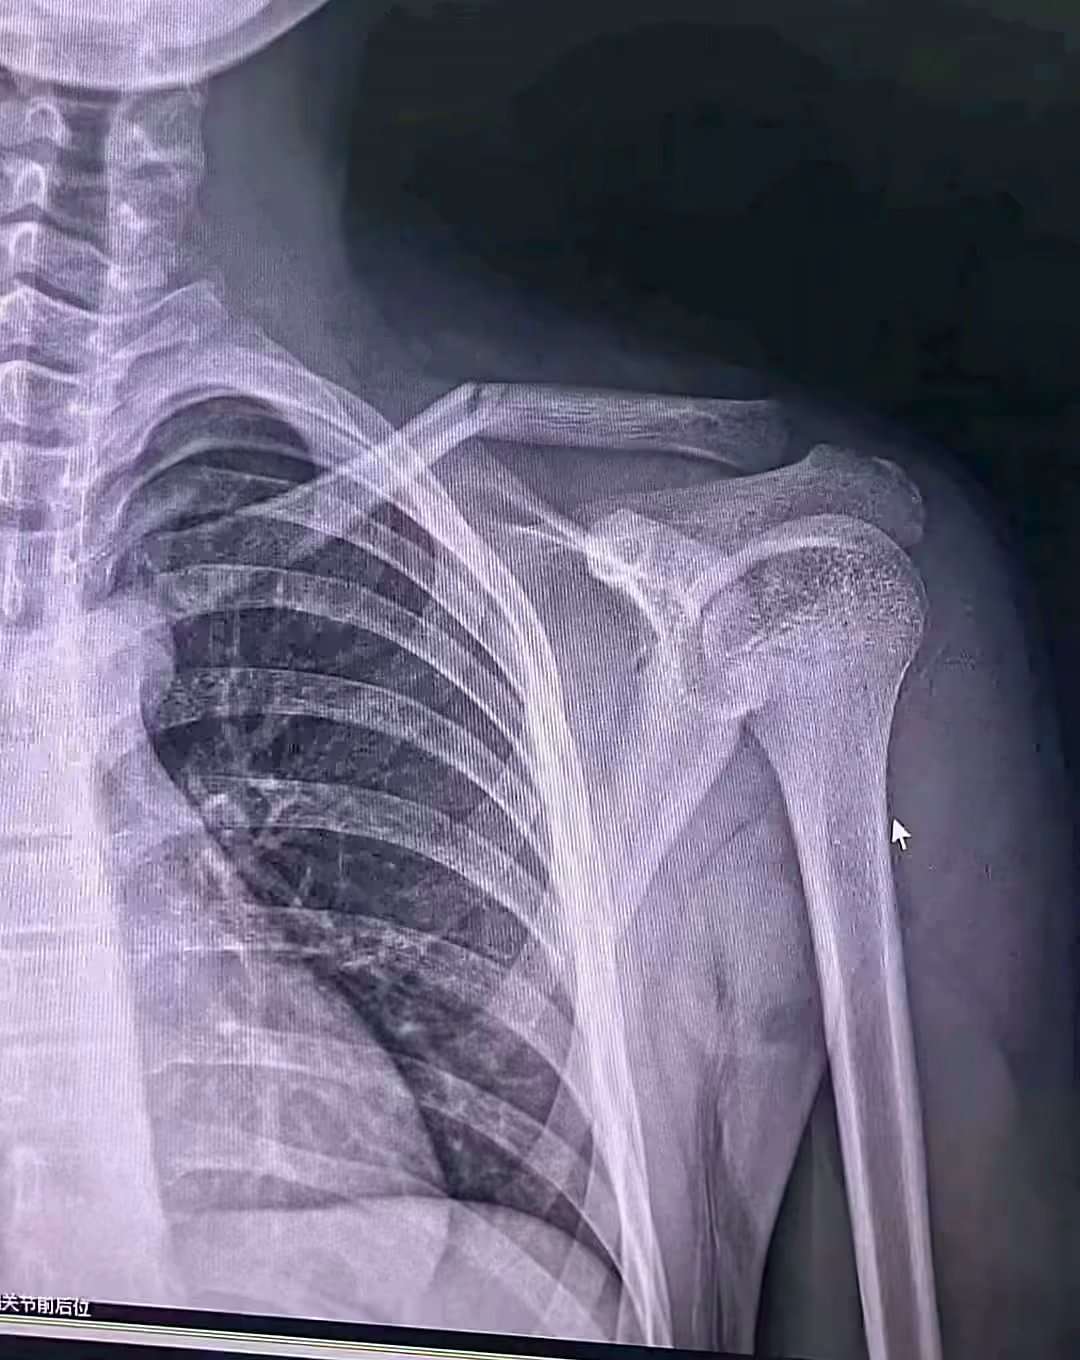

太好玩了玩骨折了